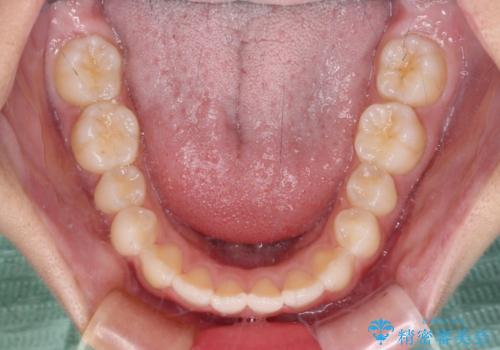

- 前歯のデコボコを気にして来院された高校生の患者様です。

捻れた前歯が前方に飛び出している点も気になっており、目立たない装置を希望されたため、インビザラインを用いて矯正治療を行うこととしました。

上下ともに少し捻れが残っていたため、治療の継続を提案しましたが、本人も親御さんも満足とのことで、治療を終えました。

捻れの改善により突出感も改善されました。